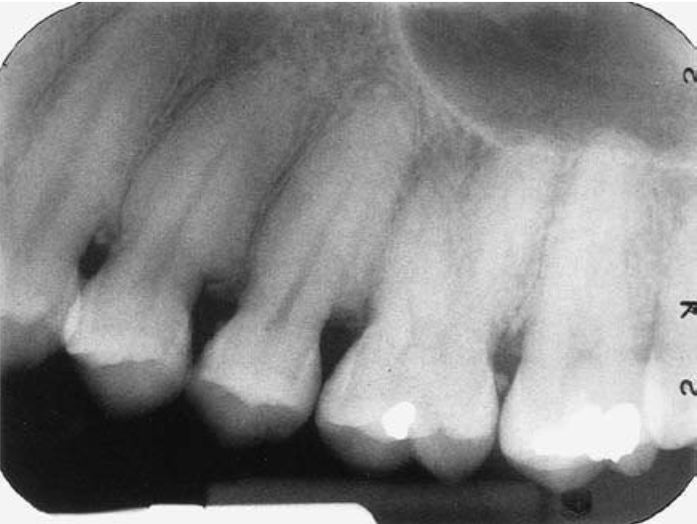

Xảy ra khi một mầm răng riêng lẻ chia đôi hoàn toàn tạo thành hai răng riêng biệt nhưng giống hệt nhau, kích thước hơi nhỏ hơn bình thường. Răng song sinh rất hiếm gặp. Răng song sinh rất khó phân biệt với răng dư. Chẳng hạn như trong hình 20.2, rất khó để xác định răng cửa bị dư là kết quả của một mầm răng sinh đôi hay phát triển từ một mầm răng dư khác mà ra.